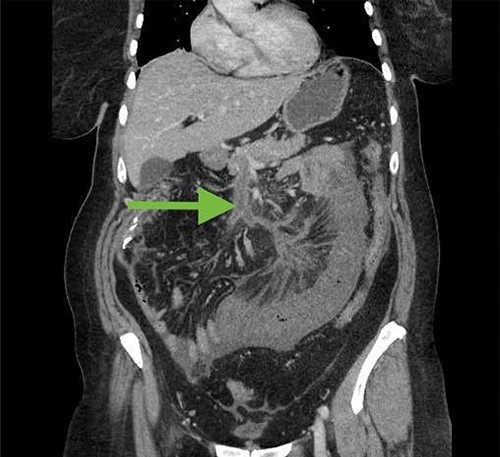

Neuroendocrine tumors are a rare, heterogeneous group of neoplasms. The incidence is about one in 100 000, although this may be increasing [3]. These tumors grow slowly and symptoms are often vague, which may lead to a delay in diagnosis. The primary treatment for small bowel neuroendocrine tumors in patients with locoregional disease is surgical resection with lymphadenectomy, although there are now several treatment options for distant metastases [4]. Metastases to the mesentery are common, and these metastases with released cytokines can lead to fibrosis. This can result in a bowel obstruction or ischemia. In one retrospective study looking at 824 patients with small bowel neuroendocrine tumors, 36 patients had apparent clinical manifestations of fibrosis, which included mesenteric vessel obstruction and obstructive uropathy [2]. There has been one reported case of cecal necrosis as a result of small bowel neuroendocrine tumor [5]. However, this is the first case of small bowel neuroendocrine tumor presenting with gangrenous appendicitis. In our patient, the patient was found to have an incidental neuroendocrine tumor of the terminal ileum with mesenteric metastases and extranodal extension. This likely caused ischemia of the appendix. In retrospective review of pathology slides from the initial operation, the patient did have small vein thrombosis present (Fig. 4), although this is not necessarily uncommon in appendicitis. From a surgical perspective, the entire appendix was inflamed, whereas most patients with appendicitis have a healthy base that can be safely divided during appendectomy. Perhaps fortuitously, this led us to proceed with ileocecectomy, which resulted in her ultimate diagnosis.

Small vein thrombosis, from initial operation (×100 magnification).